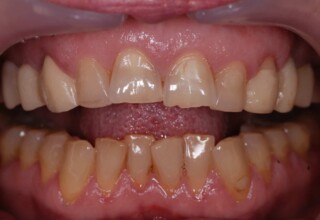

Αποκατάσταση διαστημάτων μεταξύ κεντρικών και πλαγίων τομέων

Τα διαστήματα έχουν δημιουργηθεί κυρίως λόγω των στενών πλαγίων. Μετά την ολοκλήρωση της ορθοδοντικής θεραπείας τα διαστήματα “έκλεισαν” με την τοποθέτηση δύο αποκαταστάσεων σύνθετης ρητίνης.